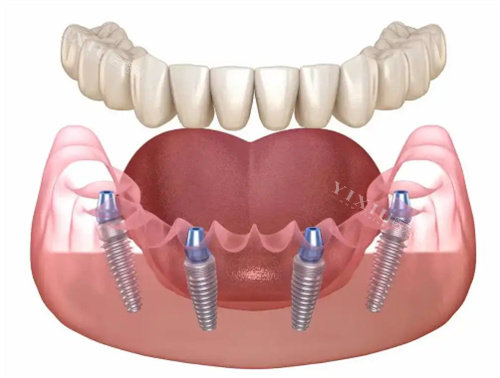

All - on - 4 半口种植牙:40000 元起

All - on - 6 半口种植牙:60000 元起

All - on - 4 全口种植牙:120000 元起

All - on - 6 全口种植牙:150000 元起